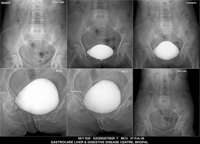

Section: URETHROGRAM

Total: 95 Cases